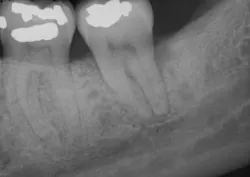

The patient returned after two weeks for a postoperative check of No. 31 and had a maintenance visit at three months post-op. At the three-month mark, the Visual-SRP area was evaluated for results. The pocket depth had resolved to 4 mm without signs of inflammation. A periapical radiograph of the area suggested bone remineralization in the site of No. 18 distal (figure 3). No. 31 was required to heal for six months and was not assessed until that time. At the six-month mark, the patient returned for another maintenance visit. The surgical area was measured, and the pocket depth had resolved to 4 mm without signs of inflammation. The periapical radiograph of No. 31 distal revealed the vertical defect was repaired, and new bone formation was evident (figure 4).

Figure 3: Periapical radiograph of No. 18 distal suggests bone remineralization, three months after nonsurgical treatment with Visual-SRP